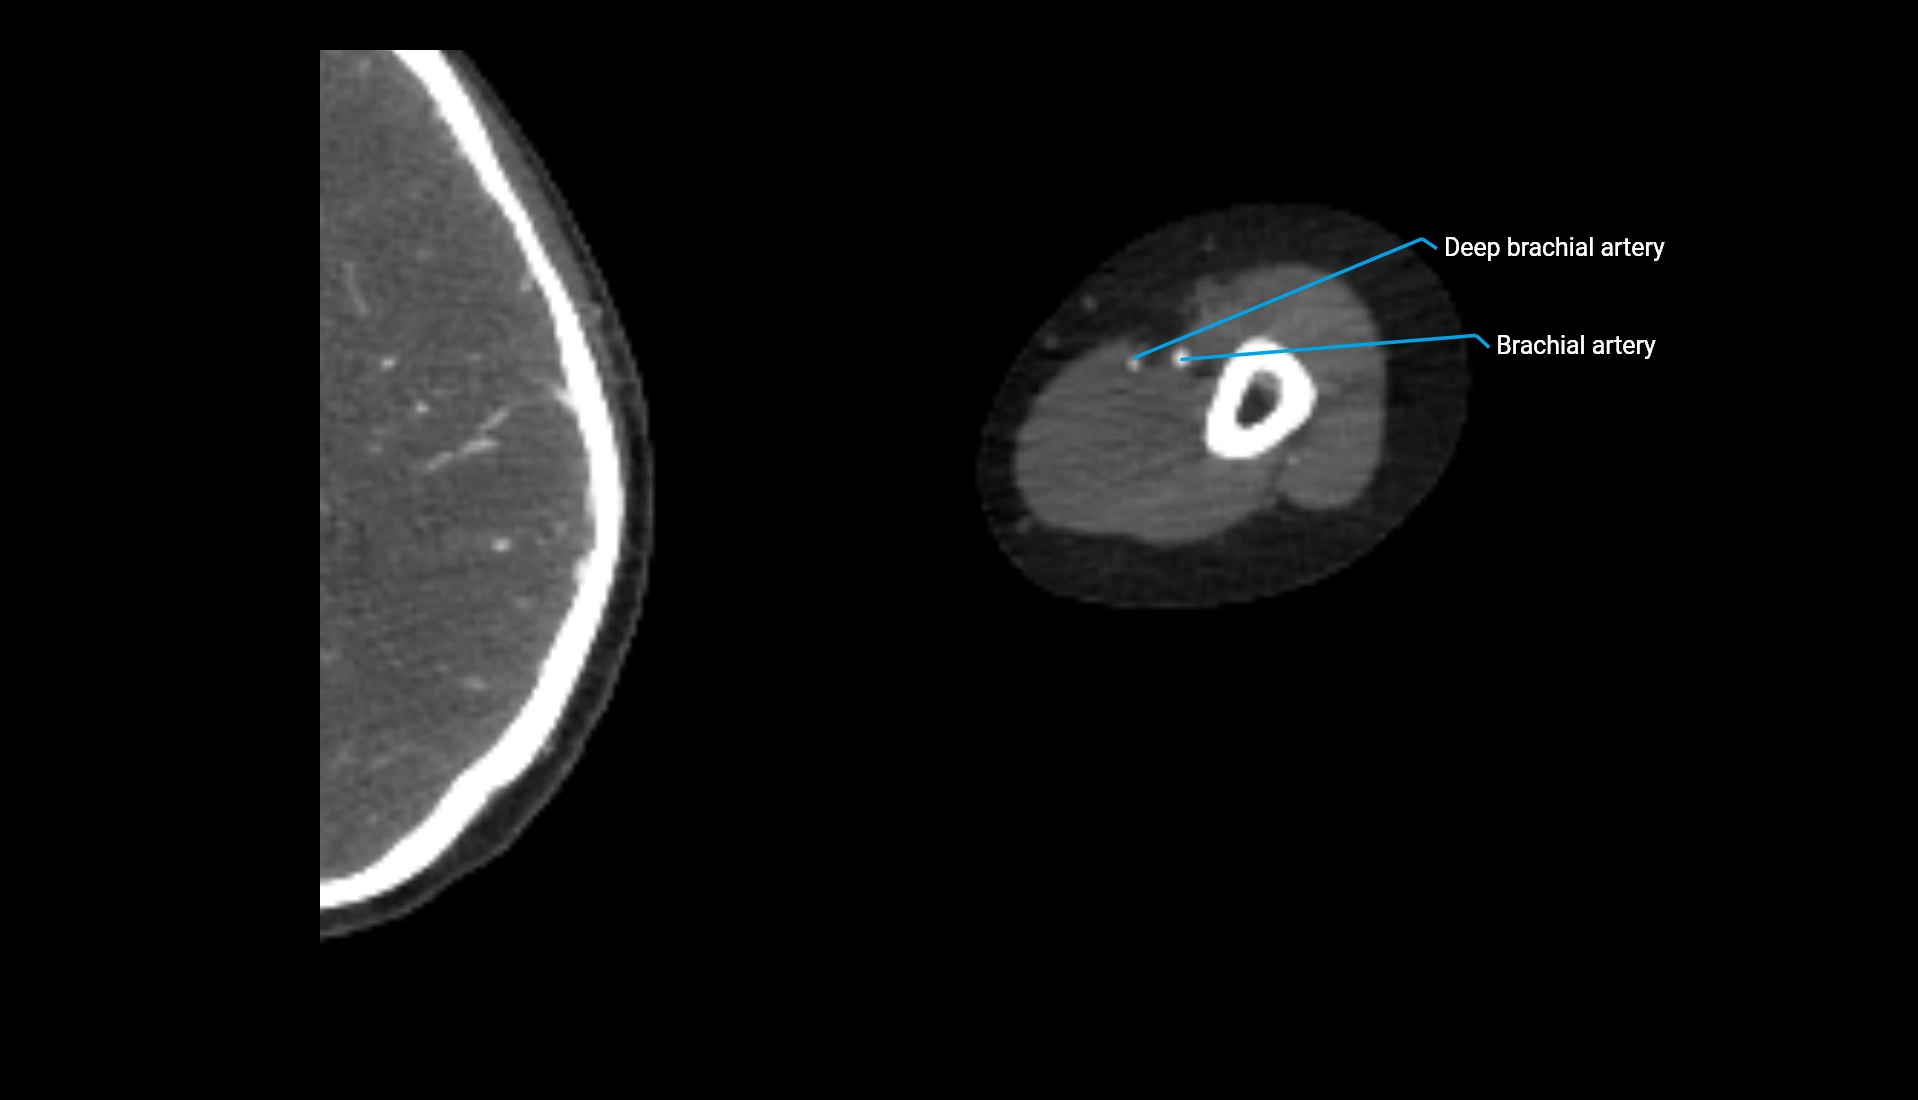

CT Appearance

Non-Contrast CT:

• Cortex: High-density, sharply defined

• Subchondral bone: Dense cancellous matrix

• Articular surface: Smooth concave contour articulating with the capitellum

• Excellent for evaluating bone integrity, alignment, and subtle fractures